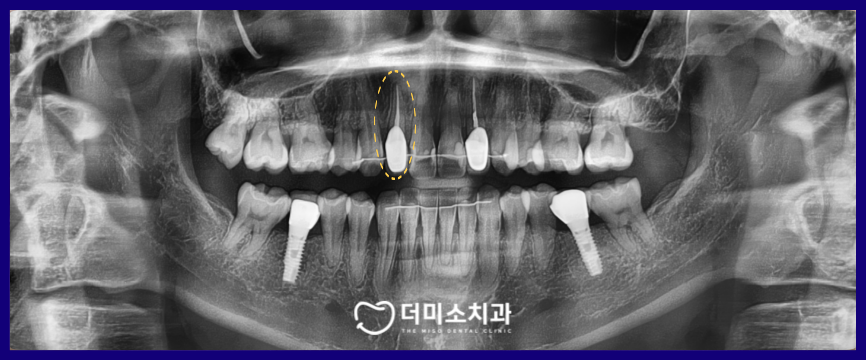

정밀한 검사를 위해

파노라마 사진을 촬영해 보았는데요.

해당 부위는 신경치료가 되어 있는 상태로

치료 자체는 문제가 없어 보였고,

주변조직에 염증소견도 없었습니다.

환자분과 같이

잇몸 라인이 검게 변하는 데에는

여러 가지 이유가 있을 수 있지만

광명동치과 더미소치과에서

면밀하게 확인 한 결과

근관 치료 부위에서 미세 누출로 인해

변색이 일어난 것으로 판단되었습니다.